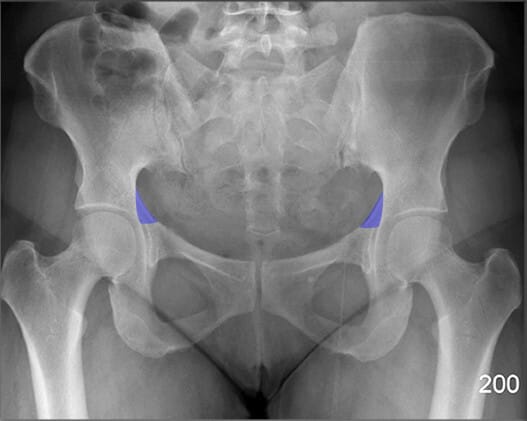

천장관절 (Sacroiliac Joint)

| 천장관절 (Sacroiliac Joint) |

| ✅ 천골과 장골 사이의 관절로, AP view상에서 좌우 대칭적으로 좁고 긴 틈으로 관찰됩니다. |

| 🔴 간격이 좁아지거나 불규칙한 경우 염증성 질환(예: 강직성 척추염)을 의심할 수 있습니다. |